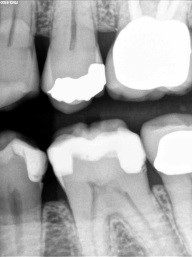

Patient 4: Teeth #12 and #13

On the black-and-white image, the patient has caries on #12, #13, #18, #19 and #20. We will focus on #12 and #13, especially the mesial of #13. The black-and-white image is less suggestive there than on #12. The photo tells a very different story. #13 is more advanced.